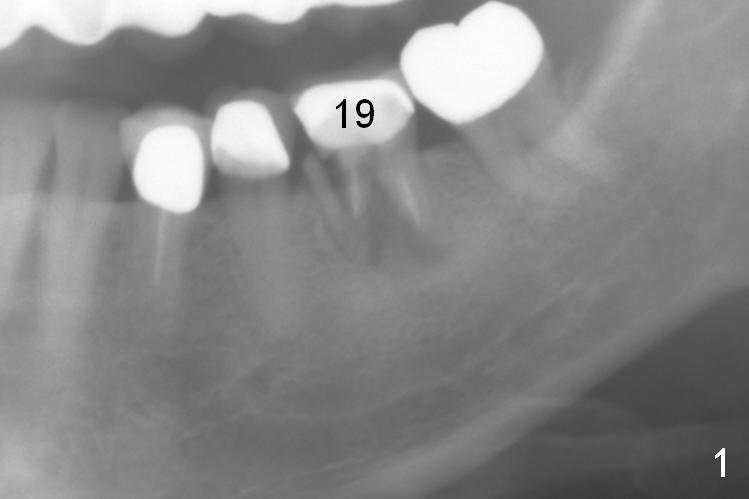

A 56-year-old lady (YW) has diabetes II, fairly well controlled. Although there is radiologic evidence of mesial root fracture of the tooth #19 (Fig.1 (panoramus)), she is asymptomatic. The buccal gingiva is slightly erythematous and edematous. There is no deep pocket. According to Fig.1, either the buccal or lingual wall is lost. This is not evident from Fig.2 (PA). Osteotomy is established in the septum or the distal socket (treated with Clindamycin), away from the lost plate (Fig.6,7). It is estimated that there is 4-5 mm apical bone. Measure the depth of the socket. Osteotomy should be 3 mm beyond the socket.